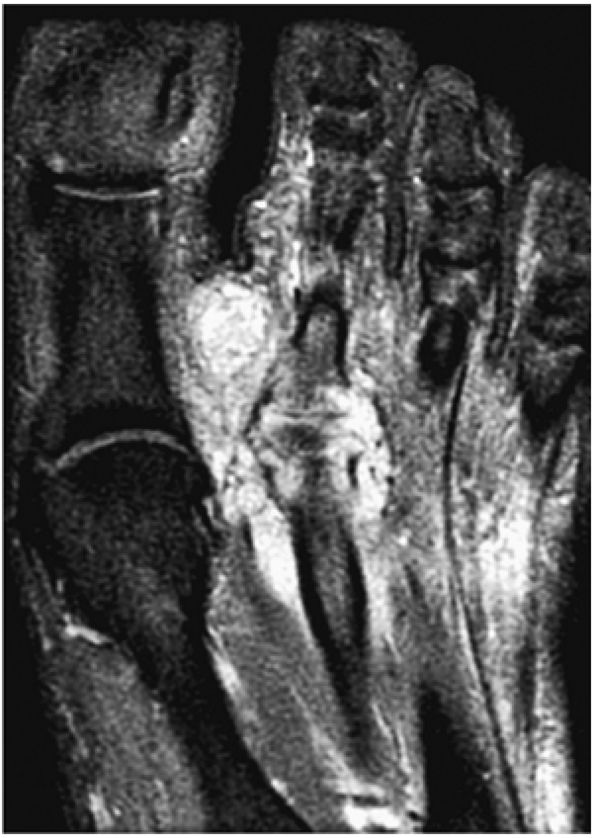

FIGURE 5.100 ● (A) Stage IV OLT with interruption of the subchondral plate, subchondral cystic change, and medially displaced chondral fragment on a coronal section color illustration. (B, C) Stage IV OLT with the displaced fragment located in the anterior tibiotalar joint capsule. The lateral OLT is the donor site. Arthroscopy is performed on all stage III and IV lesions and stage I and II lesions that fail conservative treatment. (B) Coronal T1-weighted image. (C) Axial FS PD FSE image. (D) Displaced fragment from a medial talar dome donor site in OLT on a color graphic superior view of the talus with the tibia and fibula resected.